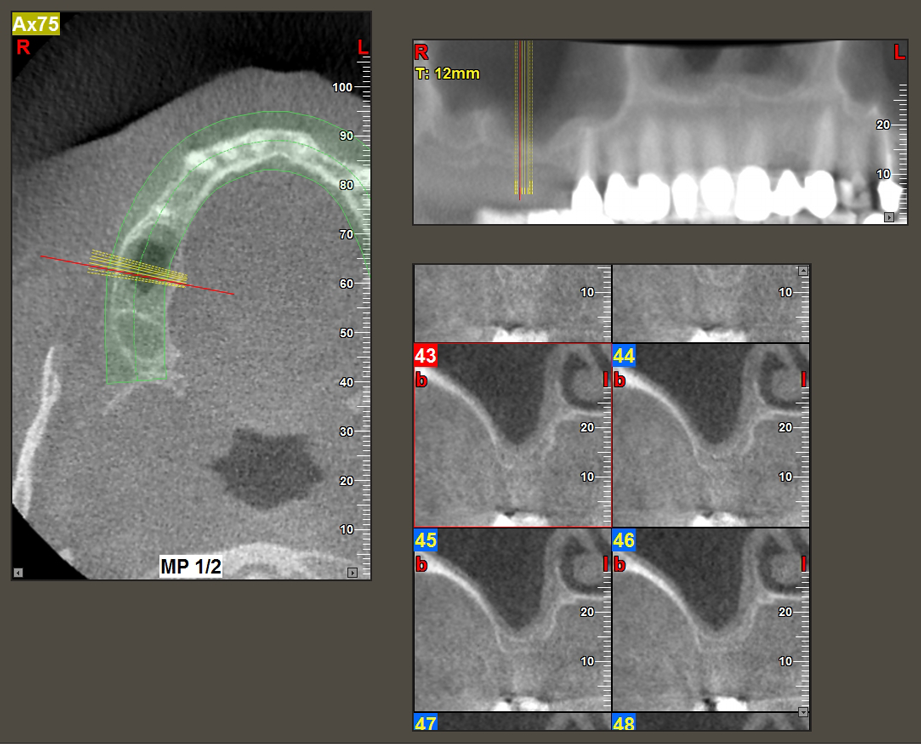

A 49-year-old female patient, a non-smoker and with nothing remarkable in her general medical history, was referred to our oral surgery practice for surgical extraction of tooth 16 and subsequent implantation. After the extraction, the patient experienced mild sinusitis trouble with the resultthat we initially waited six months before carrying out the measure. The residual bone height at the planned implant position measured 3-4 mm (Fig. 1 and 2).

Fig.2: The DVT shows adequate dimensions in each of the axial (left), lateral (top) and transverse views (right). The maxillary sinus membrane is still slightly thickened.